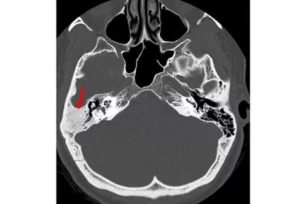

Обычная локализация в виске — каменисто-сосцевидная область. Остеома сосцевидного отростка представляет собой опухоль в нижнем отделе височной кости, за ушной раковиной. Основанием выступают воздухоносные ячейки или корковый височный слой.

Остеома может иметь компактную, хрящевую, губчатую или комбинированную структуру.

По формам выделяют:

- экзофитную, растущую кнаружи кости,

- эндофитную, когда остеома врастает в глубины сосцевидного отростка,

- компактная остеома — это частый тип структуры опухоли в височной области.